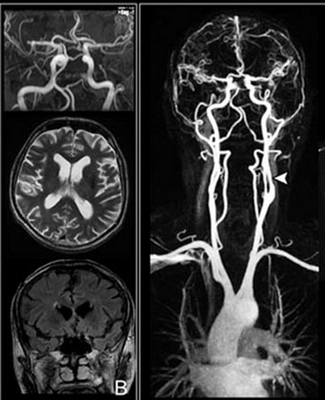

КТ сосудов головы и шеи

На томограммах четко прослеживается архитектоника сосудов исследуемой области

КТ-ангиография сосудов шеи с контрастом незаменима при травмах: скорость получения результата и отличная визуализация сосудистых катастроф, повреждений костных структур и нервных тканей позволяют быстро определить тактику ведения пациента. Большинство патологических процессов протекают генерализованно (атеросклероз, аутоиммунные заболевания), поэтому необходимо исследовать одновременно сосуды головы и шеи на предмет характера поражения и степени выраженности заболевания. На томограммах можно увидеть:

аномалии развития сосудов;

аневризмы до и после разрыва;

острые нарушения мозгового кровообращения в каротидном и вертебробазилярном русле (геморрагические или ишемические инсульты) и их причины;

возможные артериовенозные мальформации и пр.